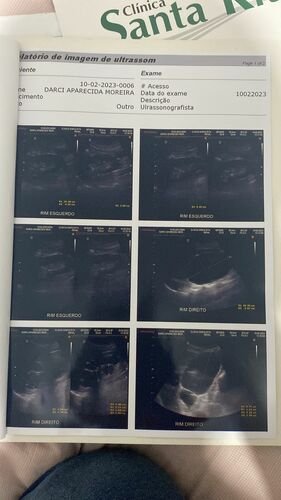

Meu nome é Bruna criei está vaquinha no intuito de ajudar minha tia Darcy que no momento não tem condições de pagar por uma tomografia que ela necessita fazer com urgência, por motivo do qual através de ultrassom e exames não conseguir descobrir o real motivo te tantas dores fortes que vem sentindo e as idas de várias vezes ao pronto socorro por dor. E pelo SUS não faz a tomografia que ela necessita como podem ver no exames o médico pede com urgência…. Agradeço desde já que Deus abençoe a todos que contribuírem..